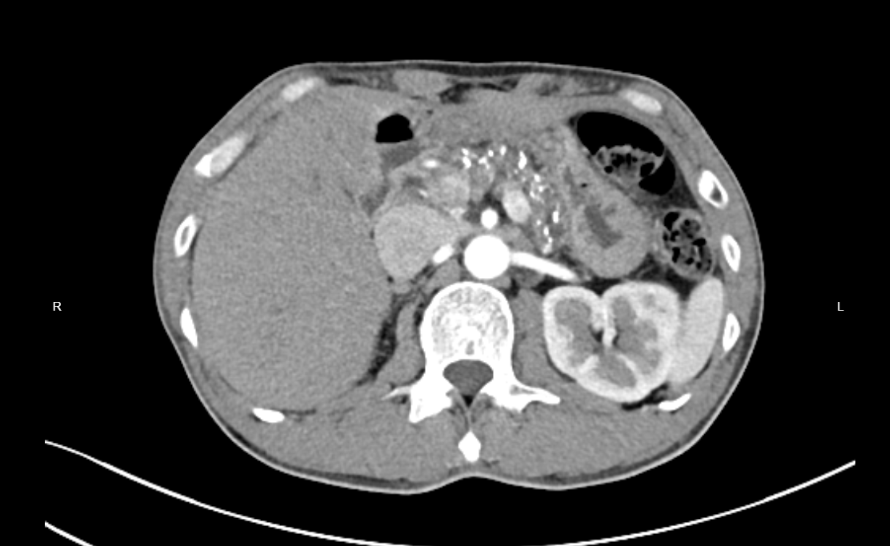

(图一:胰头部占位)(图二:胰腺多发结石)

最新一例患者是49岁男性王先生。 他长期饱受胰腺炎、糖尿病困扰,近期因上腹不适检查发现胰头部囊性肿瘤、胰腺结石及慢性胰腺炎急性发作。传统手术需切除十二指肠、部分胃及胆道,创伤大、恢复慢。相比传统切除术,保留十二指肠的胰头切除术(DPPHR)创伤更小、恢复更快、术后生活质量更高,但技术难度极大——稍有不慎就可能导致十二指肠缺血坏死或胆管损伤,因此对主刀医生的解剖功底、精细操作能力要求极高。